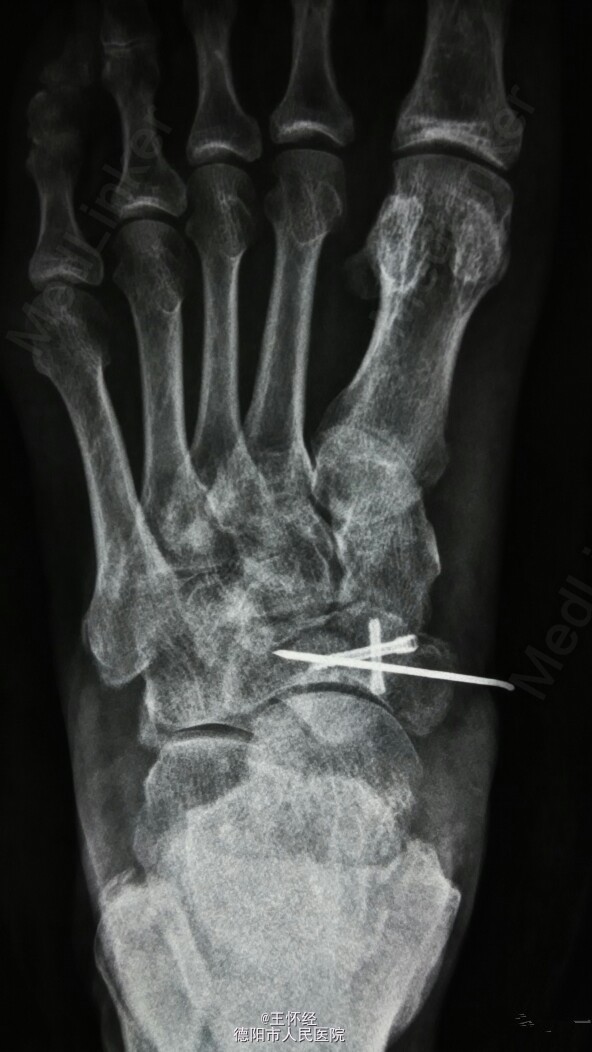

舟骨骨折

患者男性,49岁,外伤后急诊入院,发现舟骨骨骨折,行手术治疗